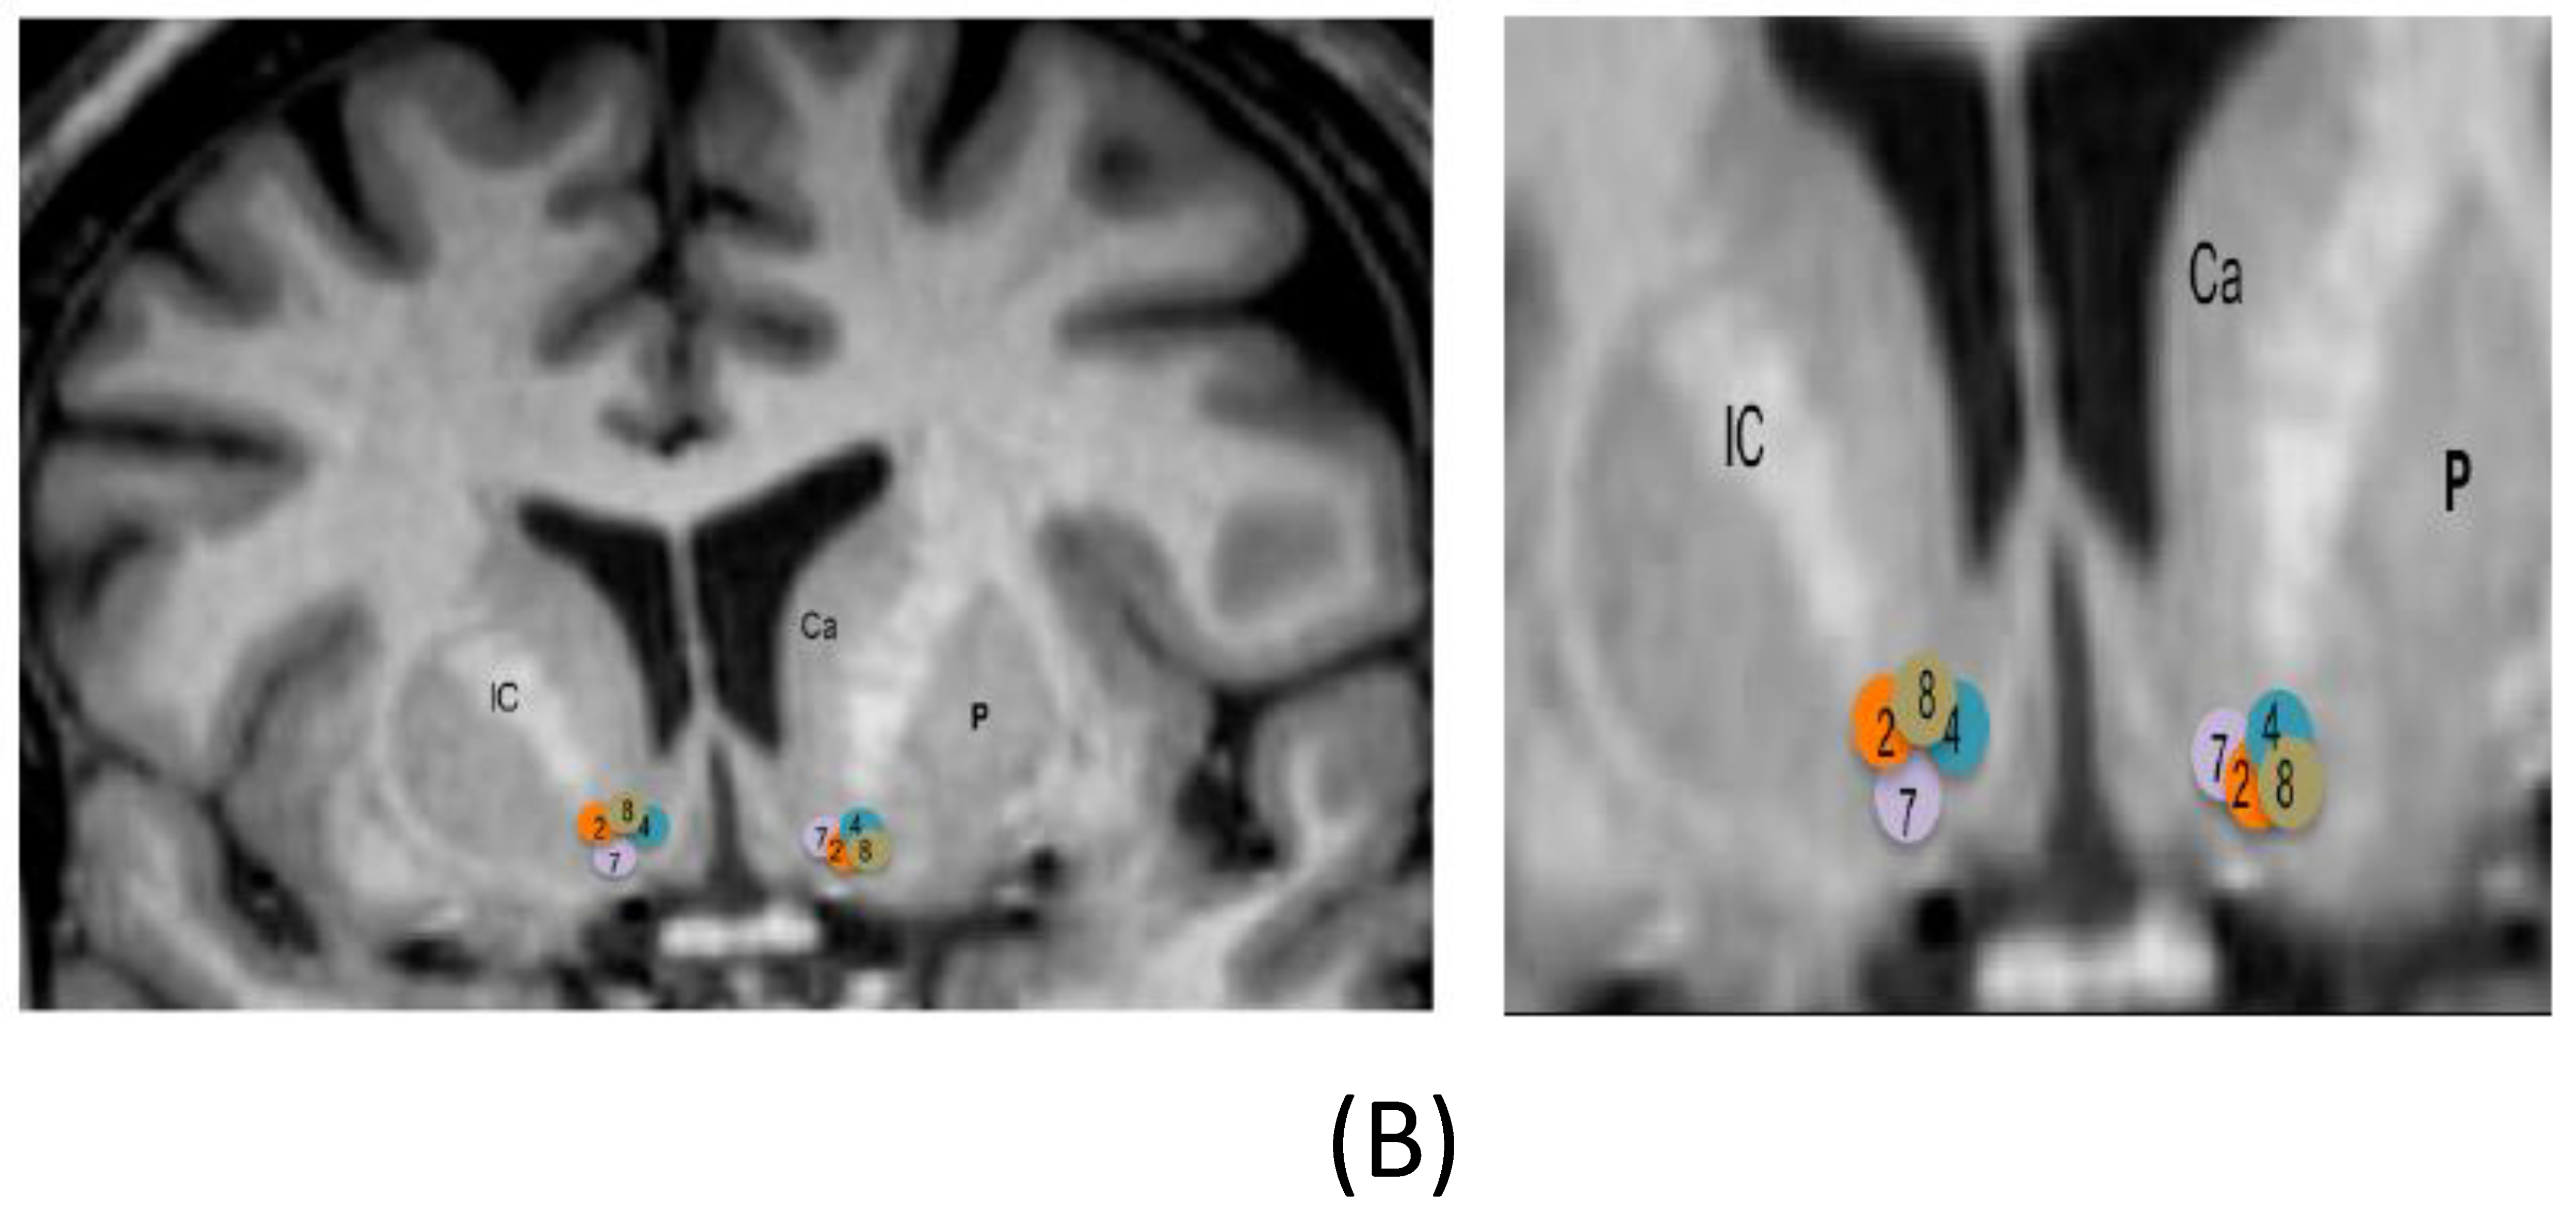

Table 1 describes the demographic and clinical characteristics of the sample, with the active contacts and stimulation parameters. Figure 2 shows location of electrode active contacts.

Figure 2. Location of electrode active contacts. (A) Location of electrode contacts on a sagittal view for patients with DBS on the subcallosal cingulate. Circles are schematic representations of electrode active contacts. Numbers within circles correspond to each patient. The figure at the right side is an enlargement. C = cingulate. CC = corpus callosum. (B) Location of electrode contacts on a coronal view for patients with DBS on the nucleus accumbens. Circles are schematic representations of electrode active contacts. Numbers within circles correspond to each patient. The figure at the right side is an enlargement. CA = caudate nucleus. CI = internal capsule. P = putamen. DBS = deep brain stimulation.